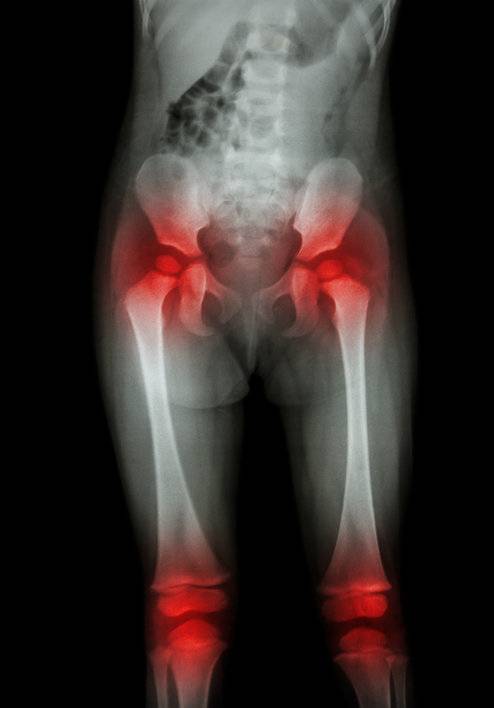

엉덩이 관절(고관절)이 뻣뻣하거나 약하면 무릎 통증의 원인이 될 수 있다는 분석이 나왔다.

엉덩이 근육이 제대로 기능하지 않으면 무릎이 그 부담을 떠안게 된다.

무릎은 앞뒤로만 움직이지만, 고관절은 여러 방향으로 움직인다.

하지만 고관절이 굳거나 근력이 약해지면, 그 기능을 무릎이 보완하게 되면서 통증이 생긴다. 특히 걷기, 달리기, 스쿼트, 계단 오르내리기 같은 동작에서 이러한 현상이 두드러진다.

산타스는 “고관절의 유연성이 떨어지거나 조절 능력이 약하면 다리의 움직임이 비정상적으로 변하고, 이로 인해 무릎이 과도한 부담을 받는다”고 설명했다.

엉덩이 바깥쪽 근육이 제 역할을 하지 않으면 허벅지뼈(대퇴골)가 안쪽으로 휘고, 이로 인해 무릎 안쪽에 부담이 가해진다.

또 골반의 움직임이 비정상적이면 대퇴골과 정강이뼈(경골)가 비틀리며 무릎 관절 내에 마찰이 생긴다.

이런 상태가 지속되면 연골 손상이나 슬개대퇴통증증후군으로 이어질 수 있다.